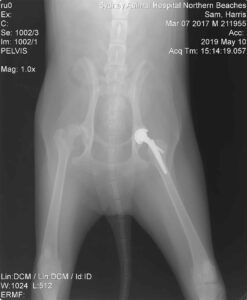

Once on the operating table the specialist surgeon Dr. Andrew Levien confirmed yet again that Sam had significant osteoarthritis and his left hip was completed luxated. With our team of vets and nurses closely monitoring Sam’s vitals throughout the procedure, Dr. Andrew removed the femoral head and neck. A prosthetic hip joint and femoral head were then surgically attached, replacing the hip joint entirely. The final step to the procedure involved taking a set of radiographs to ensure the implant was in the proper position.

Finally Sam was ready to head home where his family continued the hard work keeping him confined and using his special cape to help him get around. After his ten weeks of bed rest were up the last set of x-rays were performed. With the approval from the Veterinary Specialist of Sydney team, Sam could final be released from bed rest and back to normal activity.